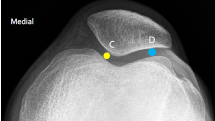

Q what is the top measurement? and what is the average + range?

A: Femoral Angle (Knee)

assesses the lateral angle between the femoral shaft and condyle lines. The average is 81°, with a range of 75-85°.

Q what is the name of the bottom measurement? and what is the average + range?

A: Tibial Angle

assesses the lateral angle between the tibial shaft and plateau lines. The average is 93°, with a range of 85-100°.